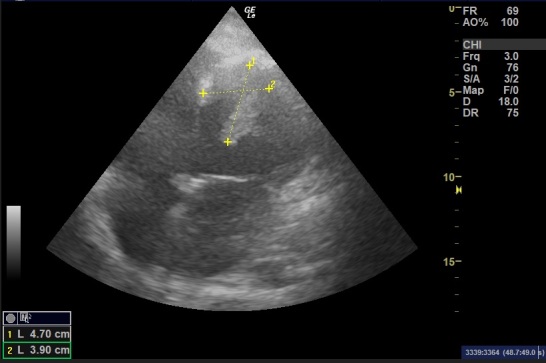

一名患有缺血性心肌病的42岁男性出现急性双侧股动脉栓塞。在对双侧股动脉进行栓子切除术和筋膜切开术后,经胸超声心动图检查发现左心室(LV)有两个梗阻性高流动性血栓。考虑到手术风险,建议采用抗凝治疗而不是手术。然而,出血风险阻碍了抗凝治疗的继续,导致血栓增大。患者随后出现多器官功能衰竭和弥散性血管内凝血病,最终不治身亡。我们还系统地查阅了 PubMed 和 Scopus 数据库中的左心室有蒂血栓病例,分别检索到 74 篇和 63 篇报道。其中,37篇相关报道(45例)加上人工检索的11篇报道被纳入数据提取,除我们的病例外,共有56例。根据病因和风险,左心室血栓是可以预测和预防的,尤其是在缺血性事件后。一旦确诊,需要明确的诊断算法和警惕的随访以及多学科管理。

A 42-year-old male with ischemic cardiomyopathy presented with acute bilateral femoral artery embolization. After management with embolectomy and fasciotomy in both femoral arteries, transthoracic echocardiography revealed two pedunculated highly mobile left ventricle (LV) thrombi. Given the procedural risk, anticoagulation therapy was recommended over surgery. However, the bleeding risk impeded the continuation of anticoagulation, which increased the thrombus size. Multiorgan failure and disseminated intravascular coagulopathy followed and the patient died. We also systematically reviewed the PubMed and Scopus databases for pedunculated LV thrombi cases and retrieved 74 and 63 reports respectively. Of these, 37 relevant reports (45 cases) plus 11 reports from the manual search were included for data extraction, a total of 56 cases besides our case. Based on the etiologies and risks, LV thrombi are predictable and preventable, especially after ischemic events. A clear diagnostic algorithm and vigilant follow-up are needed as well as multidisciplinary management once a diagnosis is confirmed.